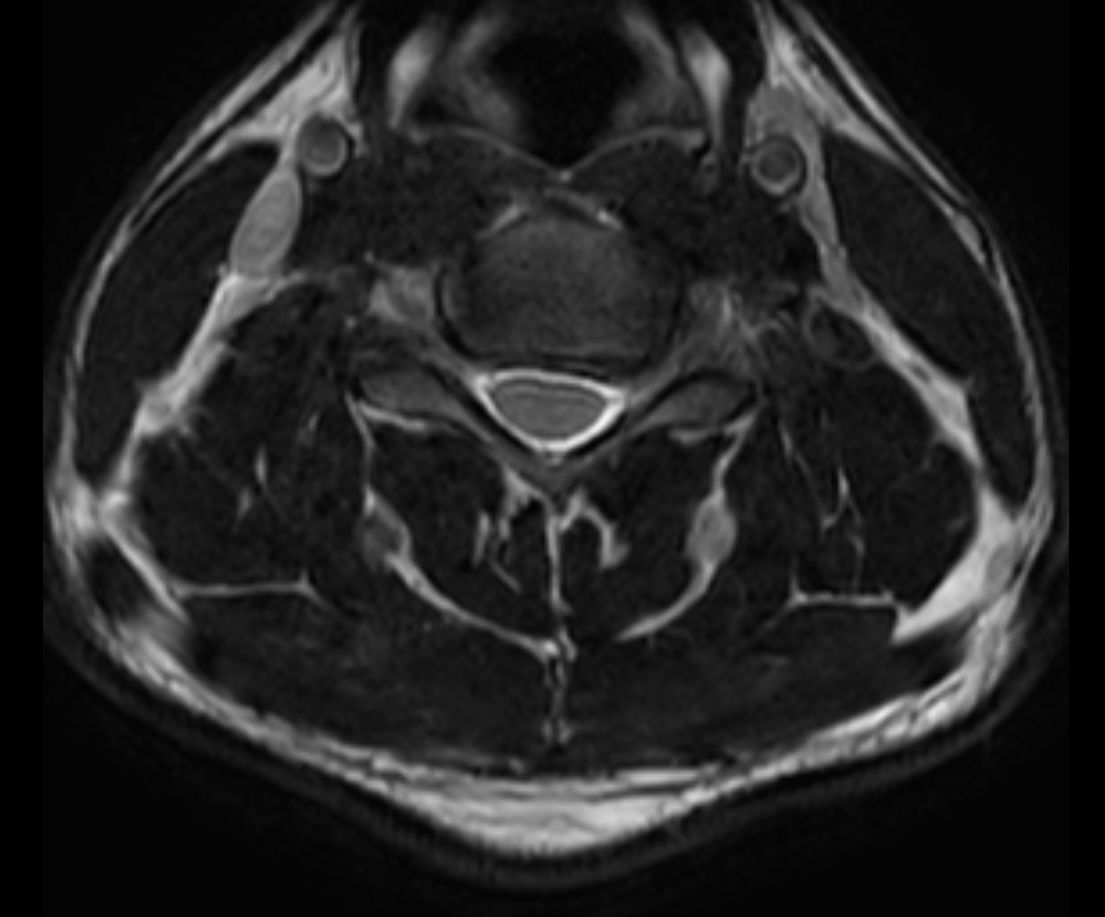

T2w TSE mDIXON XD (Fat only)